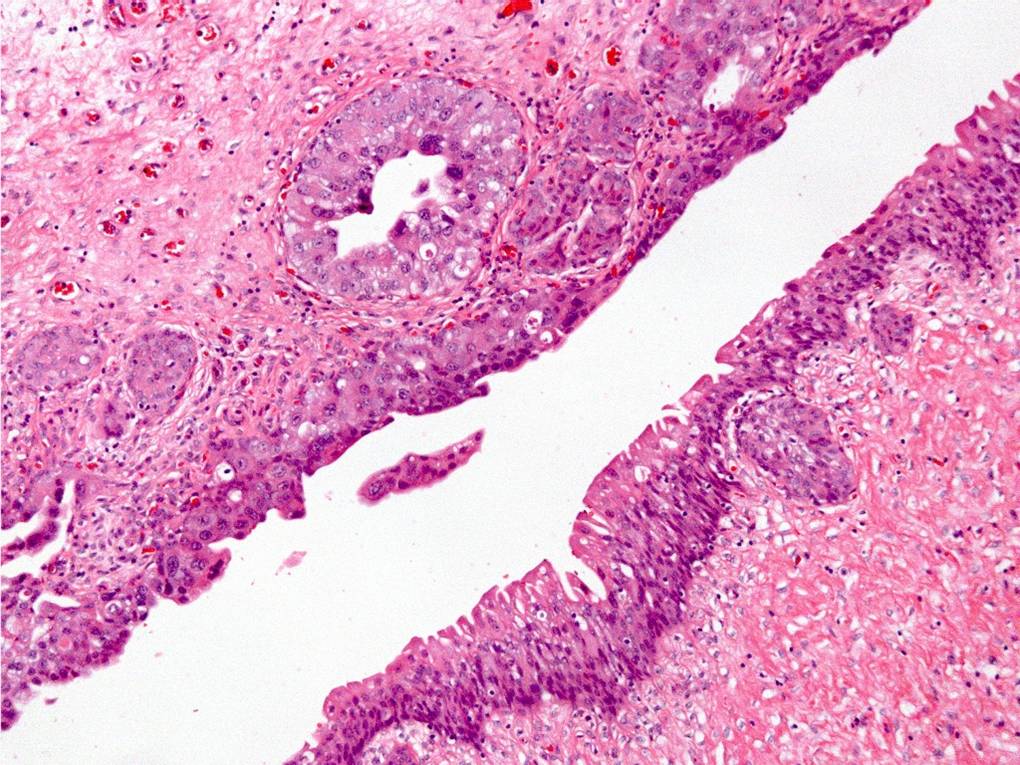

Bladder Flat Lesions

Case ID: 145